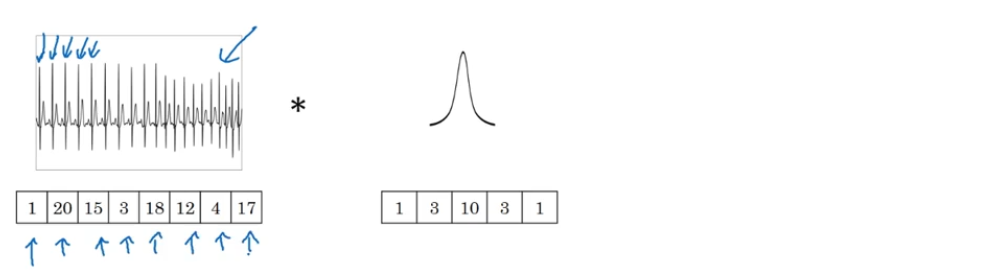

事实证明这些想法也同样可以用于1维数据,举个例子,左边是一个EKG信号,或者说是心电图,当你在你的胸部放置一个电极,电极透过胸部测量心跳带来的微弱电流,正因为心脏跳动,产生的微弱电波能被一组电极测量,这就是人心跳产生的EKG,每一个峰值都对应着一次心跳。

如果你想使用EKG信号,比如医学诊断,那么你将处理1维数据,因为EKG数据是由时间序列对应的每个瞬间的电压组成,这次不是一个14×14的尺寸输入,你可能只有一个14尺寸输入,在这种情况下你可能需要使用一个1维过滤进行卷积,你只需要一个一维的过滤器,而不是一个5×5的。

二维数据的卷积是将同一个5×5特征检测器应用于图像中不同的位置,你最后会得到10×10的输出结果。1维过滤器可以取代你的5维过滤器,可在不同的位置中应用类似的方法。

再一次如果你使用多通道,在这种场景下可能会获得一个14×1的通道。如果你使用一个EKG,就是5×1的,如果你有16个过滤器,可能你最后会获得一个10×16的数据,这可能会是你卷积网络中的某一层。

所有这些方法也可以应用于1维数据,你可以在不同的位置使用相同的特征检测器,比如说,为了区分EKG信号中的心跳的差异,你可以在不同的时间轴位置使用同样的特征来检测心跳。

所以卷积网络同样可以被用于1D数据,对于许多1维数据应用,你实际上会使用递归神经网络进行处理,这个网络你会在下一节课中学到,但是有些人依旧愿意尝试使用卷积网络解决这些问题。